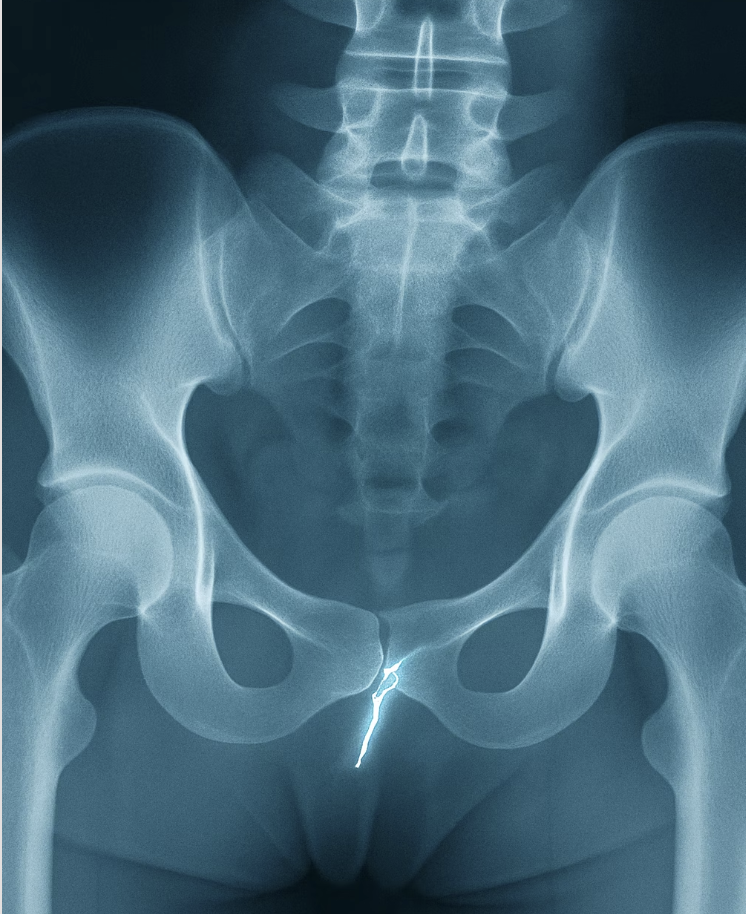

하지만 통증이 줄어들지 않고 계속되거나, 앉고 일어서는 것조차 힘들 정도로 극심한 경우, 혹은 배변 시 항문 주변까지 찌르는 듯한 통증이 느껴진다면 꼬리뼈 골절이나 탈구를 강력하게 의심해 봐야 합니다. 스스로 판단하지 말고, 반드시 ‘정형외과’를 방문하여 X-ray 촬영을 통해 정확한 상태를 확인하는 것이 무엇보다 중요합니다.

A. 뼈와 관절, 인대 등 근골격계 문제를 전문적으로 다루는 ‘정형외과’를 방문하는 것이 가장 좋습니다. X-ray 촬영을 통해 뼈의 상태를 가장 정확하게 확인할 수 있습니다.